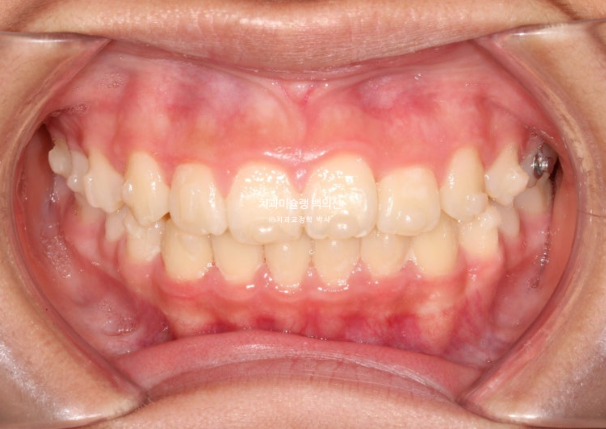

25.07

중심선은 잘 맞고

어금니 교합은 물샐틈 없는 1급 교합관계를 보입니다.

이제 전 후 비교해 보겠습니다.

총 치료기간은 1년 6개월이고 중간에 중심선 이슈로 잠시 쉬는 시간이 4개월 있었습니다.

재제작은 총 2회 했습니다.

24.02~25.07

치료결과가 어린이 교정이 아닌 정식 성인교정 치료 결과에 준한만큼 유지장치도 철저히 들어갑니다.

어긋난 중심선이 맞아졌으며 기울어진 앞니 치축도 좋아졌습니다.

앞니가 깊게 물리는 과개교합도 좋아졌습니다.